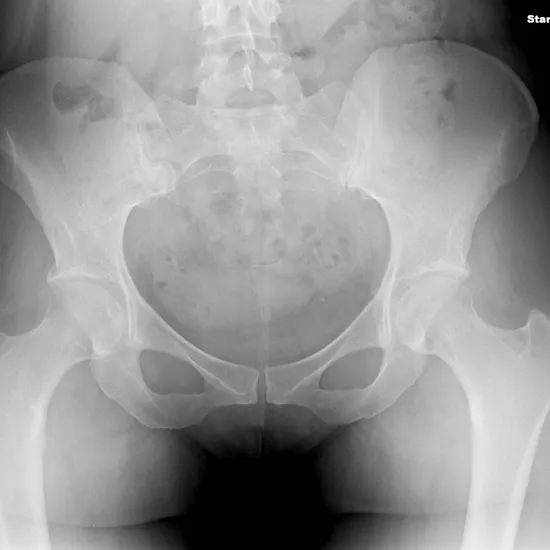

An X-ray of the pelvis is a safe and painless way to see the hip bones, the top part of the thigh bone, the hip joint, and the skin and muscles.

This test helps find any broken pelvic bones, like the hip bone and the top part of the thigh bone, and checks how the broken bone is healing after it has been set. It also helps find infections, osteoporosis, deformities, or abnormal growth of the bones in this area. It can also help find hip dislocations.